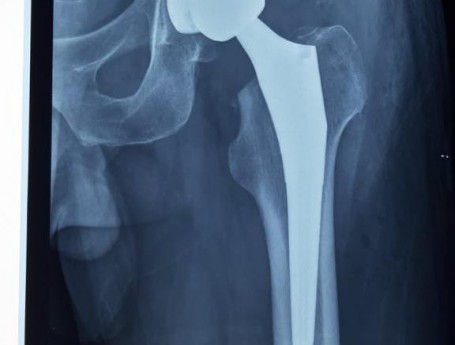

Total Hip Arthroplasty Anterior Approach

Revision Total Hip Arthroplasty Femoral Stem